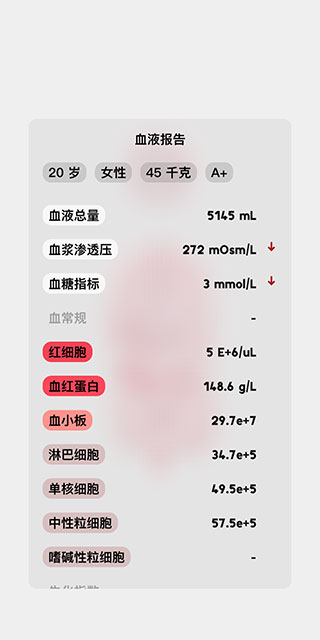

9、点击左下角的红色血滴图标,会显示该人体模型的具体血液报告,里面包含了各项专业指标。

8、屏幕右上角显示的是该人体模型的异常状态,例如现在,她正处于低血钾和低血糖的状态中。